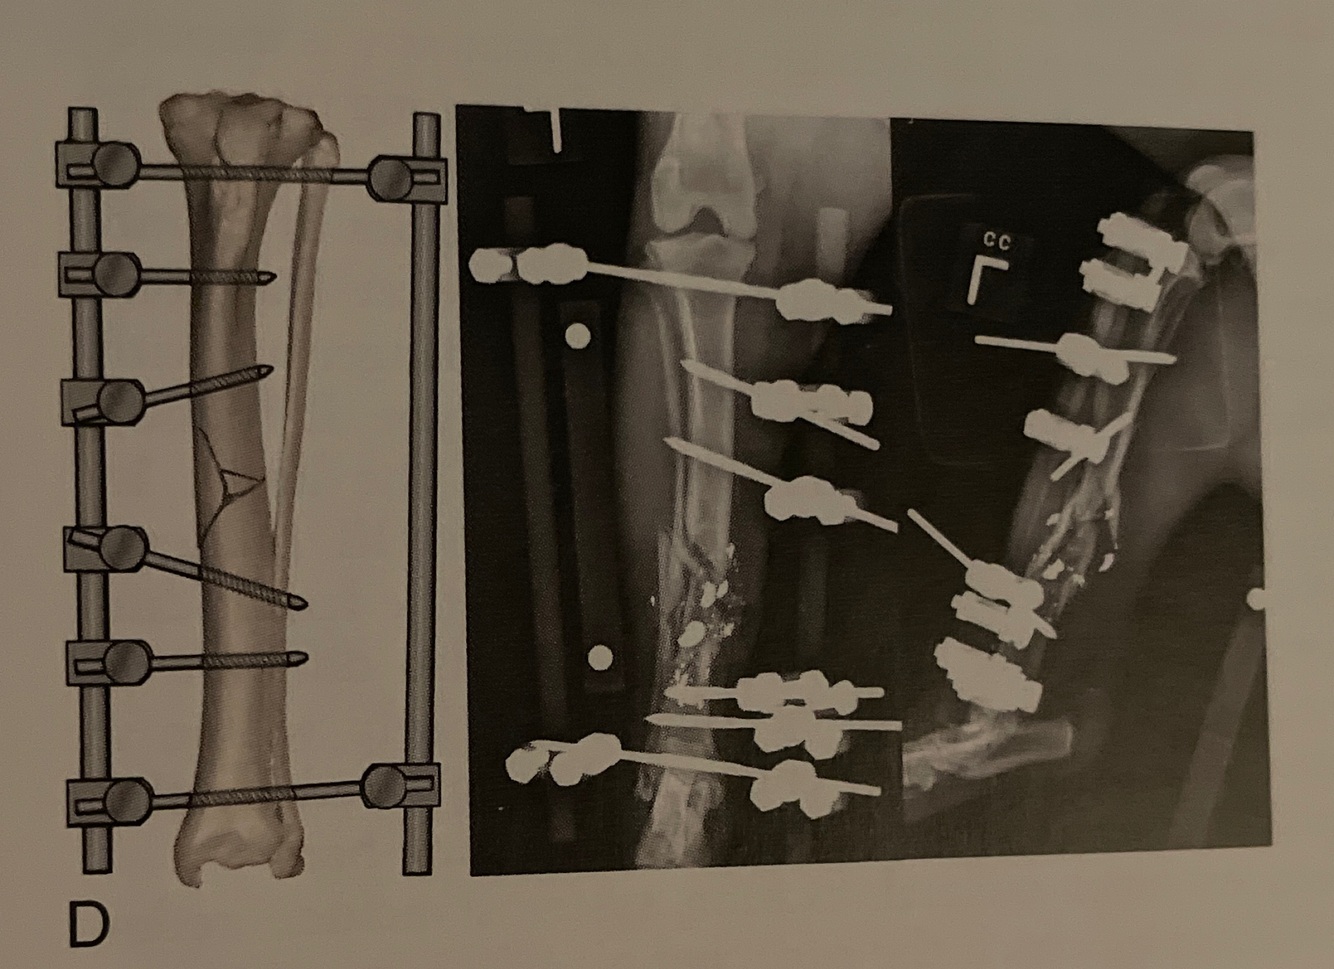

Type: III modified

Pins: Half and full

Connecting Bars: 3

Pin Geometry:

-Bilateral biplanar